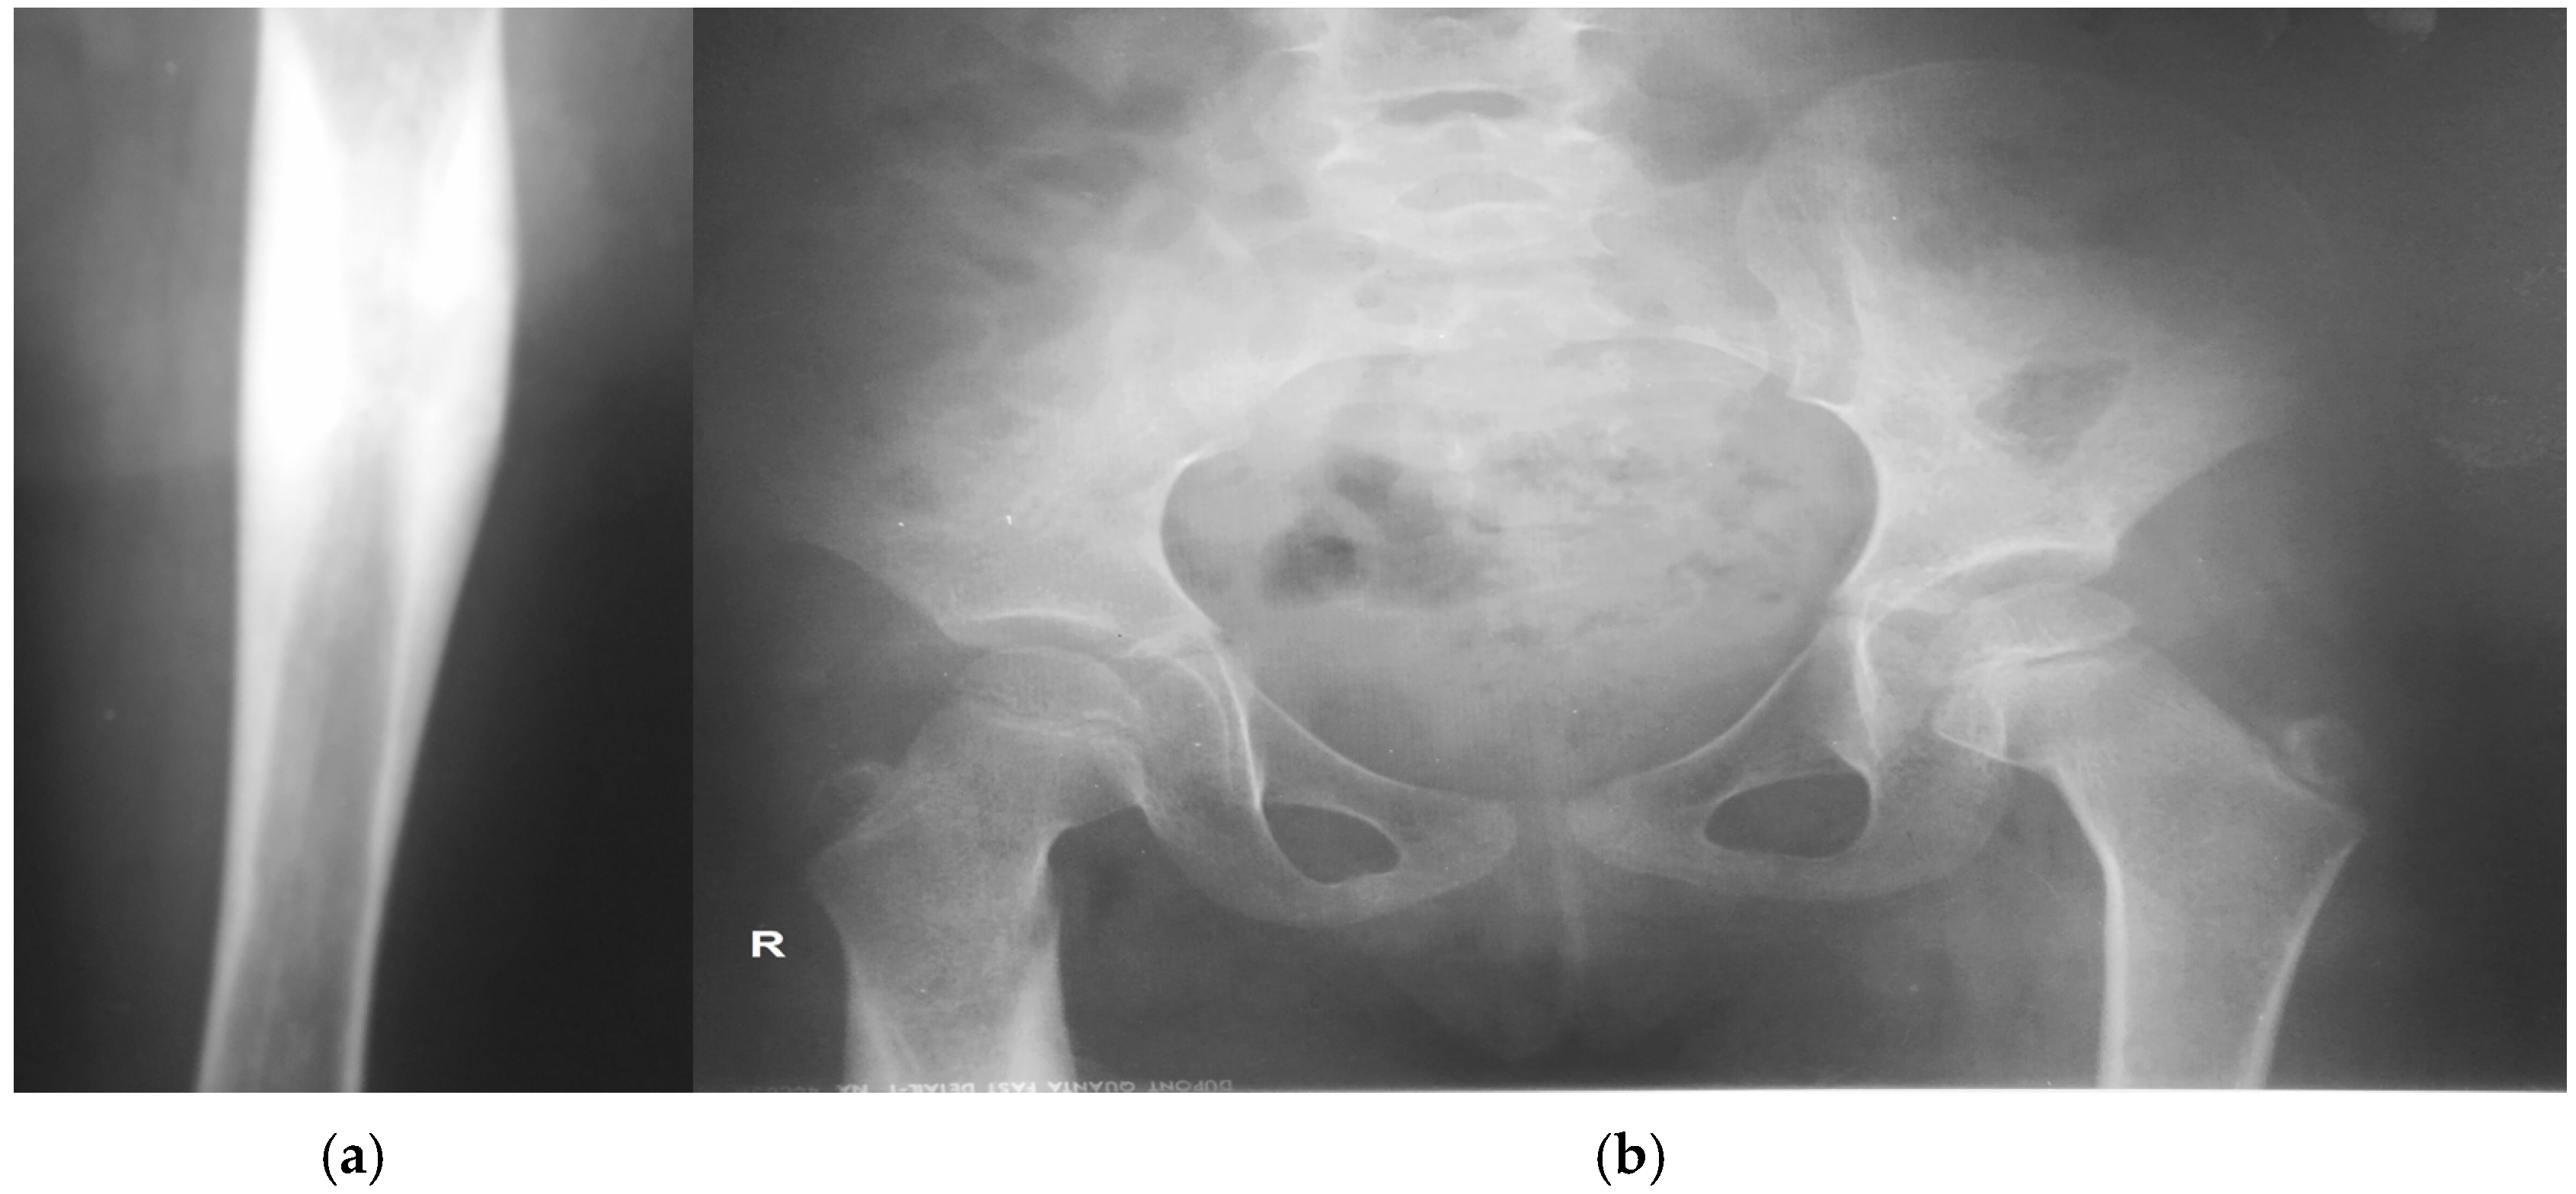

Chronic Sclerosing Osteomyelitis of Garré of the Femur in a 4-Year-Old Girl Caused by Coagulase-Negative Staphylococci: A Case Report

2. Case Presentation